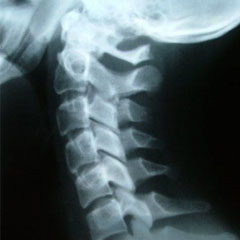

Digital Xray

We utilize state-of-the-art digital X-rays to evaluate and document musculoskeletal injuries accurately and effectively. We have the capacity and expertise to perform routine and specialized views, including standing, long-leg, and full-spine X-rays. We can incorporate X-rays made in other facilities into the patient’s digital file.